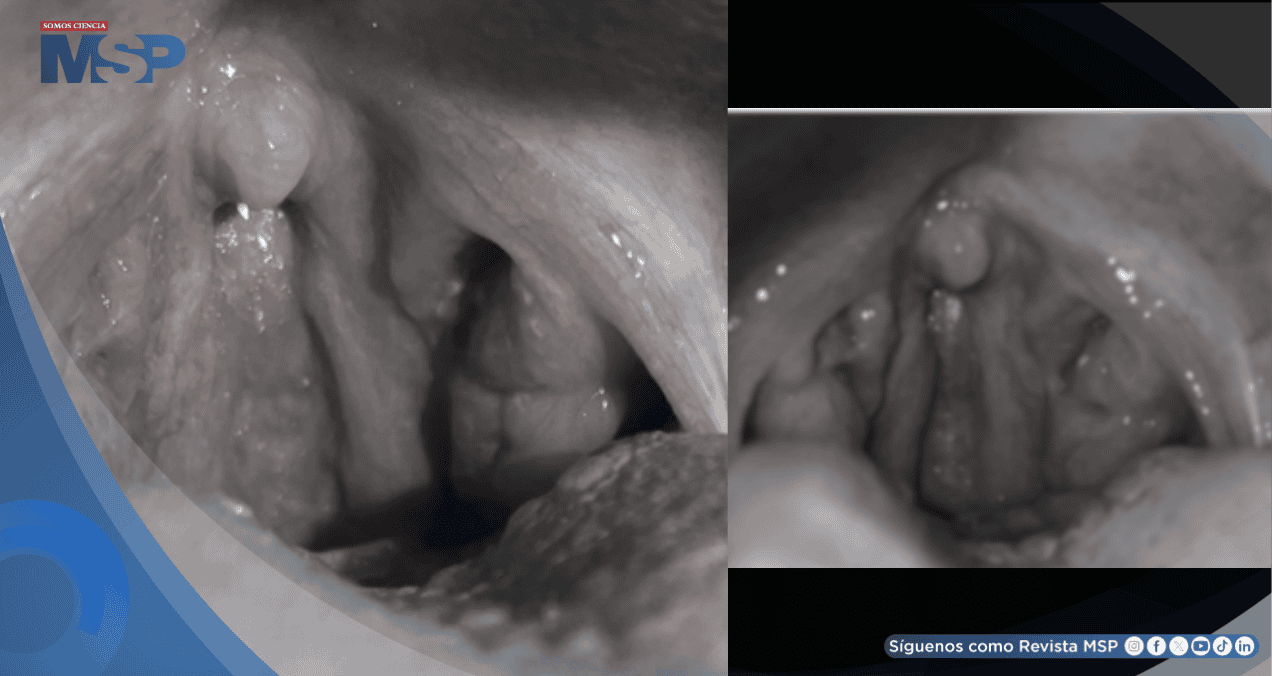

El examen físico realizado durante este episodio reveló una mucosa faríngea enrojecida con folículos linfáticos prominentes. Ambas amígdalas se observaron inflamadas y eritematosas. No se palparon ganglios linfáticos aumentados de tamaño en el cuello.

La paciente presentaba febrícula (estado subfebril). Estos síntomas agudos remitieron aproximadamente a los diez días, nuevamente sin haber recibido tratamiento antibiótico. La afección recurrió en dos ocasiones más a lo largo del embarazo. De forma paralela, se observó de manera persistente la presencia de tonsilolitos (cálculos amigdalinos) que no causaban dolor.